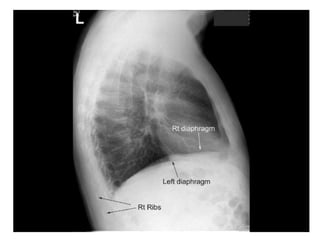

Lateral Film

Left Lateral

Right Lateral

Diaphragm

Right hemidiaphragm slightly higher than the

left